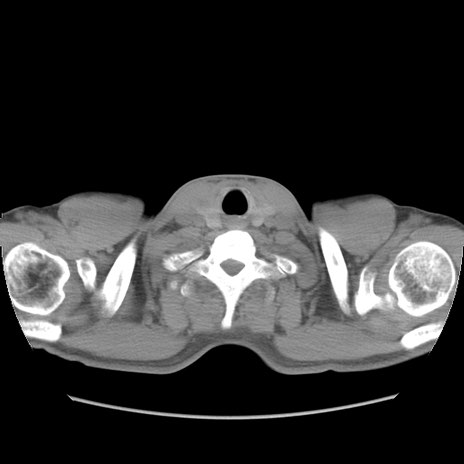

症例56 CT(横断像)

脂肪ウインドウ